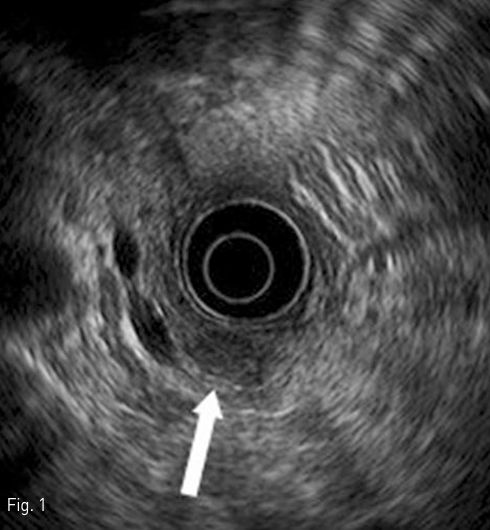

먼저 우 경정맥을 천자하여 sampling 용 5Fr Cobra catheter (Cook, Bloomington, IN)를 right hepatic vein에 거치하였다. 5Fr Röshe hepatic catheter (Cook)와 2.0 Fr microcatheter (Terumo, Tokyo, Japan)를 이용하여 gastroduodenal artery, splenic artery, SMA를 superselection 하여 baseline sampling을 실시하고, 10% calcium gluconate (DaeHan, Seoul, Korea)를 5ml씩 정량으로 투여한 후 30초, 60초, 120초에 hepatic vein blood sampling을 시행하였다. 각각의 sampling은 5분간의 간격을 두고 시행되었다(Fig. 3).

Fig 3

A splenic angiogram shows subtle hypervascular tumor staining around mid-portion of splenic artery (arrow). Catheter for venous sampling in right hepatic vein was showed also (arrowheads).